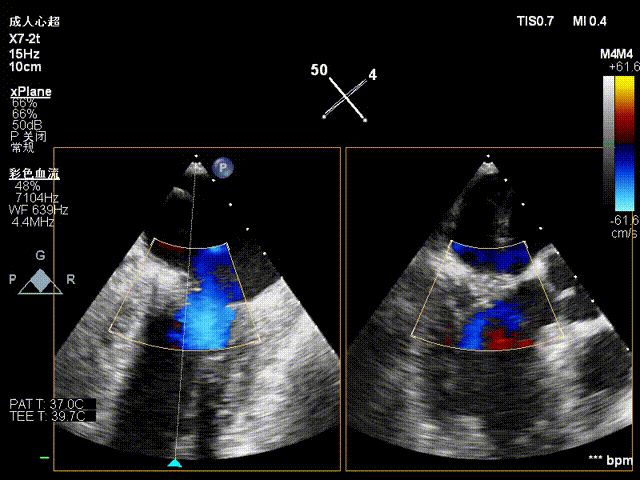

夹合后反流评估

检查示组织桥明显,夹合器稳定,残余反流明显减少,降低至1+等级,二尖瓣平均跨瓣压差为2mmHg,经团队评估,手术效果达既定预期,各项指标平稳,顺利结束手术。